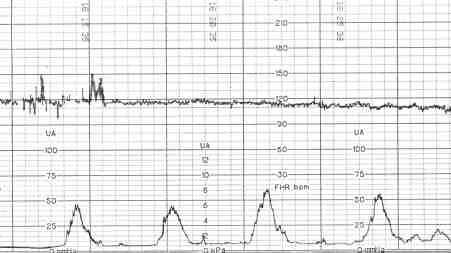

Начиная с 32-й недели все беременные должны регулярно приходить в женскую консультацию на кардиотокографию или КТГ. Что это за процедура, зачем она нужна, как проходит, как к ней готовиться и можно ли отказаться – читайте в этой статье. КТГ плода является важным методом исследования, которое проводят женщинам, независимо от того, как протекает её беременность. Это обследование помогать врачу понять и оценить сердцебиение ребёнка в состоянии покоя и в движении. Оно проводится с 32 недели. КТГ оценивает...

Одним из частых вопросов будущих мам на поздних сроках беременности является вопрос о КТГ, доктора часто советуют записаться на данную процедуру, но не объясняют – зачем. Мамы начинают переживать, что с ребеночком возникли проблемы и нервничают. Давайте подробно и доступно расскажем будущим мамам, зачем и для чего эта процедура проводится и как к ней нужно подготовиться. Зачем это делается и как? Кардиотокография или сокращенно КТГ – это регистрации сердечных сокращений ребеночка и сокращений стенки матки, если расшифровать название метода...